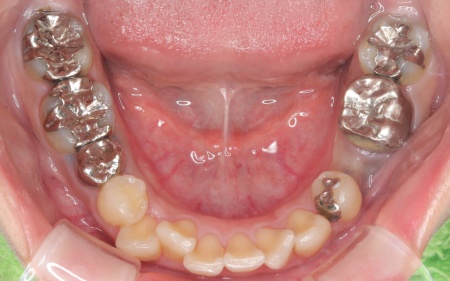

20代女性 ワイヤー矯正で歯並びを整えて虫歯治療やインプラント治療で口腔内全体を改善した症例

詳しく拝見したところ、下の前歯4本を除くほぼすべての歯に虫歯が認められました。 また、左上奥歯1本と左下奥歯1本が欠損しており、その影響で噛み合わせのバランスが崩れているため、噛んだときの痛みにつながっていると考えられます。 このまま放置すると、虫歯が進行したり、欠損部周囲の歯が動いて噛み合わせがさらに不安定になったりするリスクがあるため、虫歯を含めた口腔内全体の治療が必要だと診断しました。 |

診断結果をお伝えしたうえで、以下2つの治療方法を提案しました。 ①歯並びを整えず、必要な部分のみを治療する方法 ②矯正治療で歯並びと噛み合わせの土台を整えたうえで、口腔内全体の治療を行う方法 それぞれのメリット・デメリットをお伝えしたところ、患者様は②の矯正治療を含めた総合的な治療を行う方法を選択されました。 はじめに、歯の表面にブラケットと呼ばれるボタン状の装置を接着し、そこにワイヤーを通して歯を動かすワイヤー矯正を開始しました。治療期間中は定期的に状態を確認し、計画通りに歯が動くよう調整を重ねています。 虫歯が生じている歯に対しては、虫歯部分を丁寧に除去し、歯の形を整えました。その後、被せ物を作製するために型取りを行い、後日完成した被せ物を装着しました。 また、欠損していた左上奥歯1本と左下奥歯1本に対しては、インプラント治療を行います。 すべての治療工程を終えたあと、噛み合わせや見た目、被せ物の使用感に問題がないかなどを確認して、治療を終了しています。 |

治療前